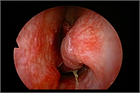

1. 鼻閉感は鼻閉塞に起因することが多いが、上咽頭疾患など鼻腔外の要因でも来し、さらに心身症や萎縮性鼻炎など、閉塞性の病変がなくても生じ得る。